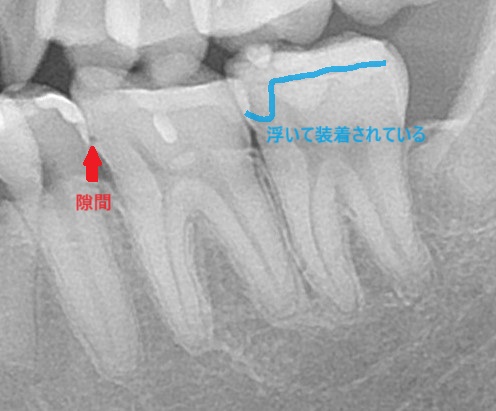

エックス線写真(レントゲン)で確認してみると、

歯とインレーの間に隙間や、ズレを認める。

担当医でやり直しはしてもらえず、当院で再治療を行う。

こちらは歯科医師の技術力による不具合。